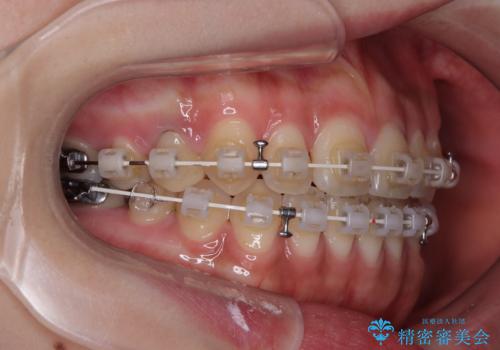

- 矯正装置

- 審美装置

- 治療期間

- 10ヶ月

治療開始から8ヶ月ほどで遠方への転勤が決まりましたが、歯列は概ね整っていたため、その後は東京出張を狙って治療を終える処置を行うことができました。